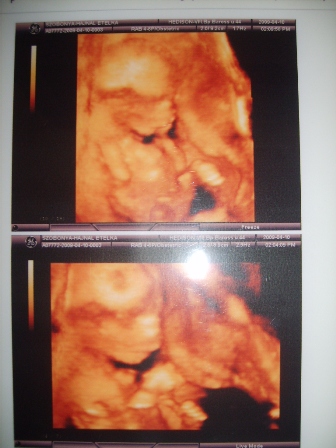

Az uh megint fiut mutatott, most mar egyertelmuen lattam en is

Viszont a kepek megint semmit sem ernek, mert nem kivankozott felenk fordulni, a kis buksijat hatulrol mutatta elsosorban, aztan oldalrol lattuk, de a kezet ott tartotta az arca elott... Persze, amikor meg a 2D fazisban mericskelte, akkor meg az ujjat is szopta, mondjuk ezt en nem lattam, csak a doki!